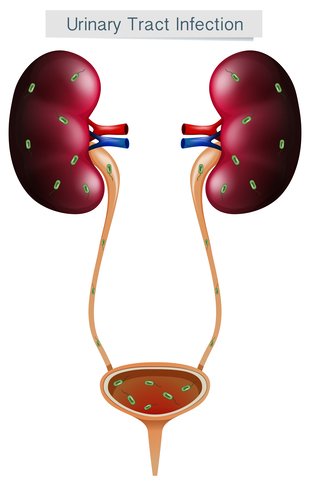

Urinary Diseases Treatment in Thane – Advanced Sol...

urology clinic healthier life patientfirst approach advanced technology urinary problems specialized treatment thane advanced solutions urinary disease treatment urinary diseases treatment effective treatment plans managing urinary conditions expert today visit offer accurate assessments infections kidney stones